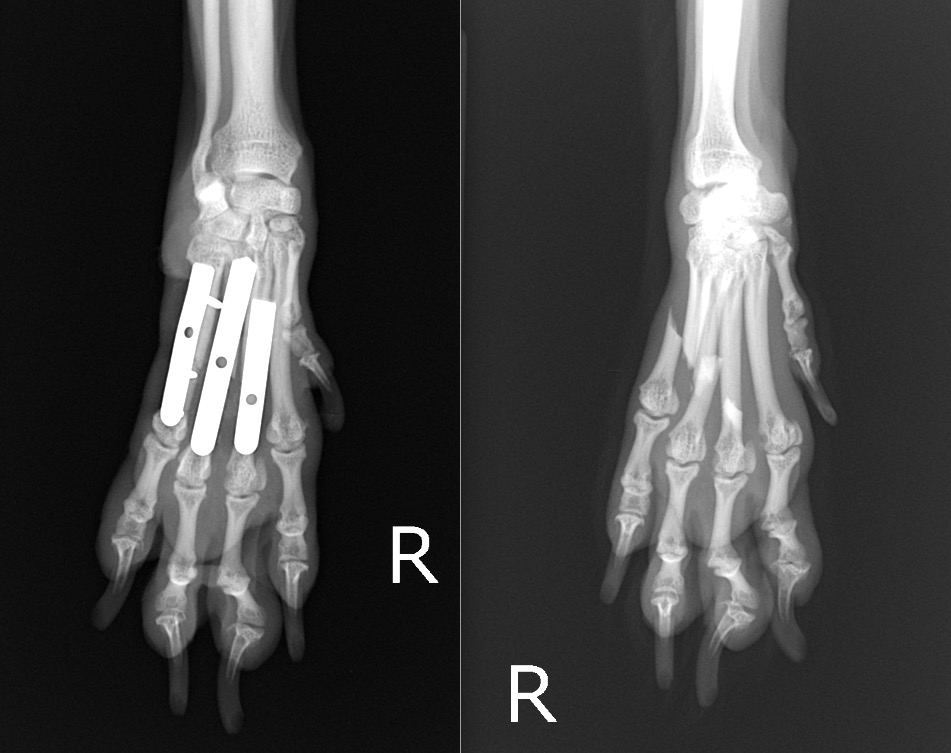

犬の中手骨骨折(1.1mmプレート使用) 左:術後/右:術前